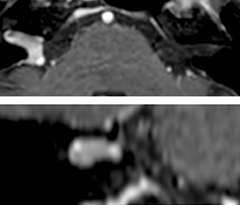

The 3D TSE T1w black blood MSDE sequence with fat suppression has an isotropic 0.8 mm voxel size and sagittal oblique and axial reformats are made. The images show superficial temporal artery thickening and peri-arterial fat infiltration. The 3D TSE PDw black blood MSDE with fat suppression has 0.55 mm isotropic voxels. The images shows focal involvement of the frontal branch of the superficial temporal artery.